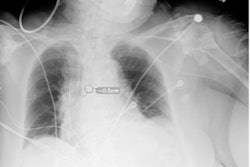

A slide presented by researchers at the ARRS meeting in Hawaii showed measurements used by an AI model for detecting correct endotracheal tube placements in x-rays of intensive care unit (ICU) patients. Image courtesy of Dr. Eui Jin Hwang.Tubes were malpositioned in 76 of the chest x-rays. In a comparison with an experienced thoracic radiologist and one trainee who independently evaluated the placements, the model achieved similar accuracy, the group found.

For deep malpositions of tubes, the model achieved an area under the receiver operating characteristic curve (AUC) of 0.96, and for shallow malpositions of tubes, the model achieved an AUC of 0.97, the researchers reported.